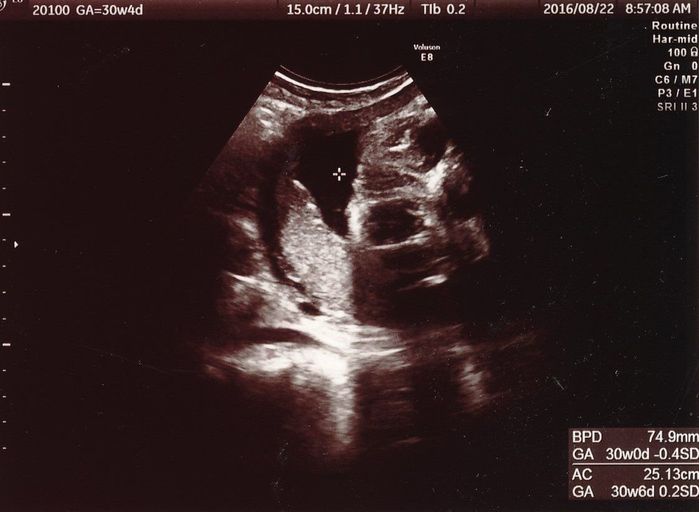

妊娠30週目のエコー写真

可愛らしさに欠けますが、中央右に顔が上下逆さまで写っています。